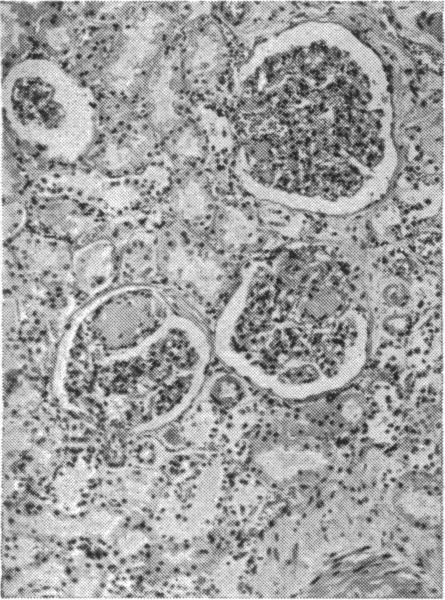

Clinical syndrome associated with Kimmelstiel-Wilson lesion of the kidney.

Br Med J. 1951 Apr 28;1(4712):916-9. doi: 10.1136/bmj.1.4712.916.